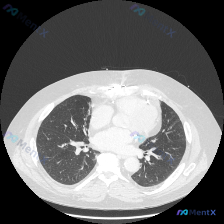

看到一个胸部CT肺窗病例,整理了一下思路。 病例资料: 这是一张胸部CT肺窗横断面图像,图像质量良好,处于胸廓上部(肺尖部下方、主动脉弓上方层面),可见气管、食管、胸骨柄、双侧锁骨头等结构。 影像表现: 1. 双肺上叶散在分布的微小结节影及斑片状磨玻璃密度影,边界相对模糊,未见明显实变或肿块。 2....